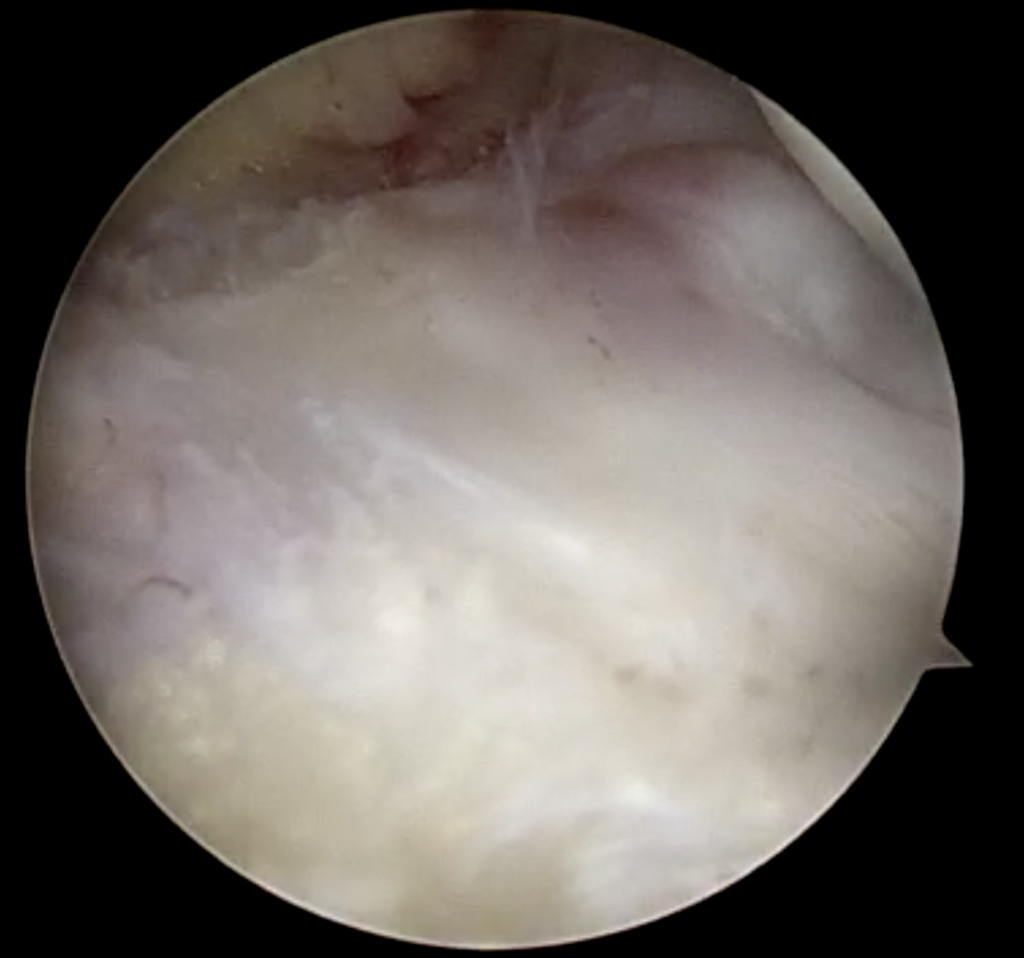

Saucerization of the redundant lateral meniscal tissue aided in the reduction of the displaced meniscus (Figure 9).

Discoid meniscus morphology contributes to a predisposition for meniscal tears. Homogenous collagen fiber organization is lost within the discoid morphology, with the periphery of the discoid meniscus maintaining a typical uniform parallel fiber orientation and the central portion having a more random fiber orientation (Bisicchia, Botti, and Tudisco 2018; Atay et al. 2007; Kim, Han, and Lee 2016). This demarcation of tissue organization was appreciated arthroscopically and used to determine level of saucerization (Figure 10). The unique histological structure likely leads to inability to resist forces while dissipating hoop stresses within the knee joint, resulting in increased tear rates with minimal trauma.